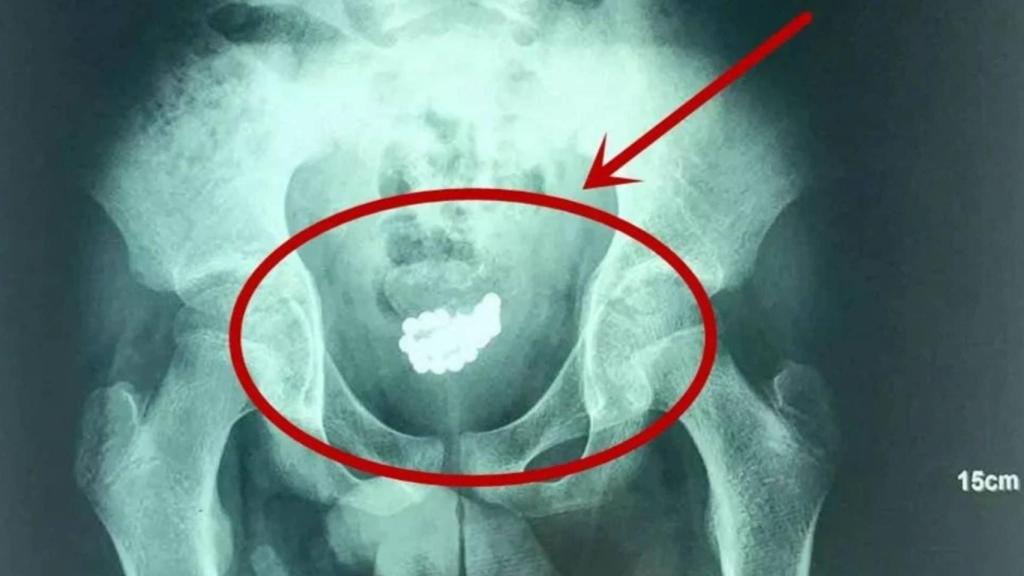

Radiografía del paciente distribuida por AsiaWire.

Sin embargo, hay situaciones que hoy en día continúan sorprendiendo a la comunidad médica, como fue el caso de Lin, un adolescente de 13 años que decidió que era buena idea meter hasta 29 bolas metálicas dentro de su pene por "curiosidad" según han informado diversos medios chinos.

Así lo admitió el joven cuando, a principios del mes de mayo, acudió al Hospital de Niños de Xi'an en la capital de la provincia de Shaanxi, en el noroeste de China. Los cirujanos lograron extraer todas las bolas metálicas, que habían estado dentro de la uretra de Lin durante los últimos tres meses. El menor se sentía tan avergonzado que no solicitó anteriormente atención médica.

Según el Dr. Zhang Yanyan, urólogo infantil que trató al adolescente, se introdujo las bolas de metal en su uretra cuando "estaba jugando con ellas", y que lo hizo "por experimentar". Posteriormente se sintió incómodo y trató de sacarlas de nuevo, pero al tratarse de metal imantado algunas se agruparon y quedaron atascadas en el conducto.